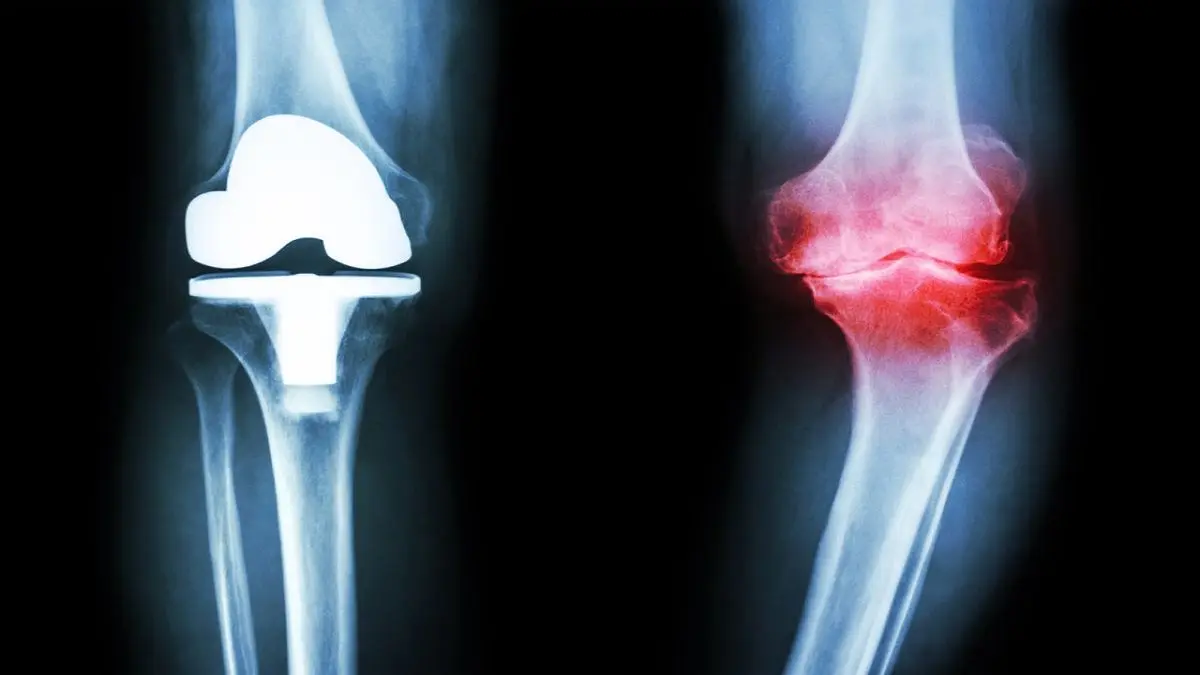

آرتروز زانو امروزه یکی از بیماری‌های بسیار رایج در میان افراد سالمند است. آرتروز مفصل زانو شایعترین بیماری تخریبی از میان مفاصل بدن محسوب می‌شود و احتمال ابتلای زنان به آن بیشتر از مردان است. عوامل زیادی مانند: کهولت سن، مسائل ژنتیکی و وراثتی، نوع شغل، چاقی، عوامل هورمونی و نژادی در بروز این بیماری دخیل هستند. در این بیماری غضروف مفصلی به تدریج شروع به تخریب شدن می‌کند و در نتیجه آن بیمار از درد شدید در زانو‌های خود گلایه دارد. حال دانشمندان موفق شده اند به روشی ساده برای تسکین درد این بیماری دست یابند.

در این تحقیقات دانشمندان به مدت ۱۲ هفته اقدام به استفاده از عصاره زردچوبه بیماران مبتلا به آرتروز زانو کردند. شواهد نشان داد به میزان قابل توجهی از درد این بیماران کاسته شده، اما تصاویر ام آر آی نشان داد مصرف این عصاره تاثیری در ساختار زانو یا بهبودی بیماری نداشته است.

در این تحقیقات، دانشمندان اقدام به تجویز روزانه ۲ کپسول به بیش از ۷۰ بیمار مبتلا به آرتروز زانو به مدت ۱۲ هفته کردند. نتایج به دست آمده نشان داد زردچوبه می‌تواند به طور قابل توجهی از علائم آرتروز زانو کاسته و درد بیماران را تسکین دهد. همچنین تورم مفاصل که یکی از اصلی‌ترین دلایل رنج کشیدن این بیماران است با مصرف عصاره زردچوبه کاهش یافت.